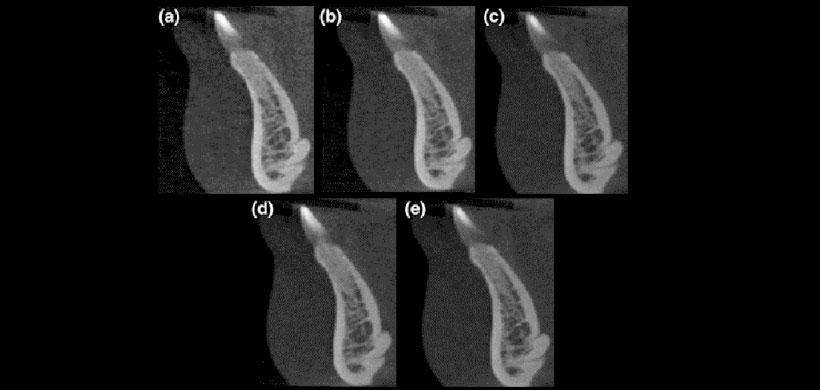

Figura 3: Canal lingual superior e inferior en diferentes configuraciones de kVp: (a) 70 kVp, (b) 75 kVp, (c) 80 kVp, (d) 85 kVp, y (e) 90 kVp